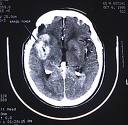

Điều trị u não và giảm triệu chứng bệnh sa sút trí tuệ: mặc dù artemisinin không thể hòa tan trong nước được, song nó có thể đi xuyên qua hàng rào mạch máu não với nồng độ cao. Do đó, người ta có thể áp dụng lợi điểm này để điều trị tiêu diệt hoặc làm chậm lại phát triển của các tế bào khối u ở não và một số bệnh lý về não màng não khác. Bên cạnh đó, trong một thử nghiệm gần đây, alkaloid của artemisia asiatica được chuyển hóa thành các phân tử nhỏ trong đường tiêu hóa và đi qua hệ thống mạch máu não. Những kết quả đó chỉ ra rằng thuốc có thể tác động như một chất ức chế acetylcholinesterase với một block beta độc tính trên thần kinh ở người gây ra tình trạng sa sút trí tuệ người lớn tuổi (Heo và cs., 2004);